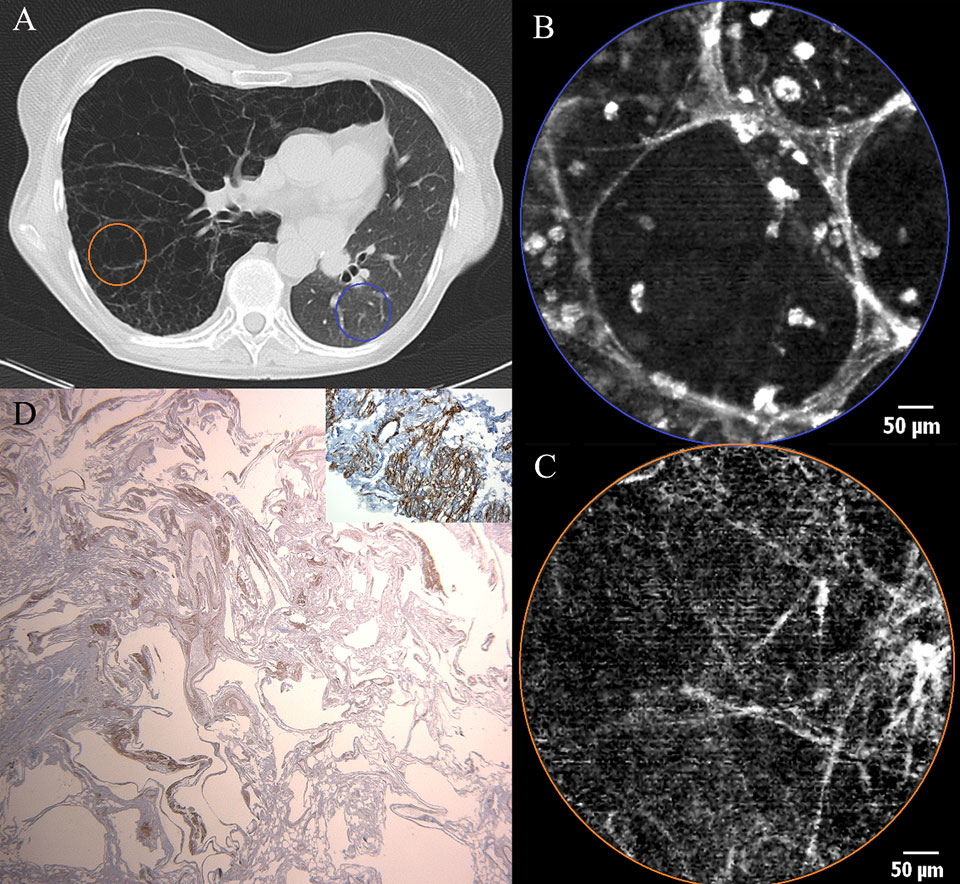

Figure 4

a) Chest CT scan of a patient with exacerbating dyspnoea, showing bilateral honeycombing with right sided predominance (filled arrow), patchy areas of ground glass opacity (open arrow) superimposed by thickened inter- and intra-lobular septal fibres. b) pCLE imaging performed ex vivo after introduction of the probe in the BAL sample. A large (200 µm) clump of fluorescent material (glycoprotein) (asterisk) is surrounded by smaller (20-30 µm) round opacities (arrow) with increased autofluorescence (macrophages). c) Histopathology on a thoracoscopic lung biopsy sample. The basic alveolar structures have been preserved (arrow). Presence of eosinophilic, PAS stain positive material containing crystalised cholesterol (asterisk).

The case of a 63-year-old non-smoking female patient with diffuse interstitial lung disease of unknown aetiology added more to this concept. Chest CT scan showed bilateral honeycombing with right sided predominance, patchy areas of ground glass opacity superimposed by thickened inter- and intra-lobular septal fibres (fig. 4a). During the flexible bronchoscopy, bronchoalveolar lavage (BAL) was performed for immunological research. When the confocal probe was inserted into the lavage fluid after bronchoscopy, the formerly described pattern was recognised, suggesting, indeed, an alveolar proteinosis (fig. 4b). Thoracoscopic lung biopsy confirmed the diagnosis of an alveolar proteinosis afterwards (fig. 4c).

Figure 5

a) Chest CT scan of a female patient after left sided single lung transplantation for lymphangioleiomyomatosis (LAM). Cystic appearance and hyperinflation of the right (native) lung due to LAM. Reduced volume of the left (transplanted) lung. b) pCLE imaging of the transplanted lung (blue area) showing a normal appearance of alveolar ducts containing some fluorescent cells. c) pCLE images of the native lung (LAM) (orange area): note that the alveolar ducts have lost their normal pCLE characteristics and only a pattern of scarce fibres is left without the ability to discern alveolar duct openings. d) Low power micrograph after smooth muscle staining (SMA). Histopathological sample of the explanted recipient lung showing cystic deformation of the lung parenchyma. Inlet : high power micrograph after SMA staining showing proliferation of smooth muscle in some areas.

Another case illustrating pCLE imaging of the respiratory tract dealt with a 54-year-old female patient with medical history of a left lung transplantation for reasons of lymphangioleiomyomatosis (LAM) (fig. 5a). On the occasion of two routinely performed bronchoscopic evaluations with a 3 month interval, pCLE imaging was performed in both native and transplanted lungs. In the left (transplanted) lung we found alveolar structures without any aberrant characteristics compared to pCLE findings in ‘healthy’ subjects (fig. 5b). Alveolar duct openings had a mean diameter of 286±81 µm, and mean septal wall thickness was measured at 4.6±1.1 µm. Although this patient was a strictly non-smoking patient (absent urine alkaloids), autofluorescent cells could be identified in the alveolar areas of the transplanted lung (mean alveolar cell count: 70 cells per microscopic field) with a mean diameter of 25.2±7.5 µm. Endomicroscopical features of the diseased native lung (right side) were totally different (fig. 5c). Alveolar ducts had lost their normal pCLE characteristics and only a pattern of scarce fibres was left without the ability to discern alveolar duct openings. Mean thickness of these fibres was measured at 3.4±1.3 µm which is significantly thinner than what was measured in the transplanted lung (p = 0.0009, unpaired t test).

In lymphangiomeiomyomatosis (LAM) a proliferation of smooth muscle cells is seen in lymphatics, arteries, veins, bronchioles and alveolar walls. In the alveolar walls, elastic fibres are progressively replaced by smooth muscle, leading to weakening of the alveolar structures and loss of elastic recoil. Alveolar walls rupture and in end-stage disease lung parenchyma is turned into large cysts (several centimetres in diameter) consisting of walls containing smooth muscle, lined by alveolar epithelium (fig. 5d). These pathophysiological events lead to a decay of elastic fibres, which explains why, in pCLE imaging of a LAM lung, the normal alveoloscopic pattern cannot be found and only thin isolated elastic fibres are visualised.